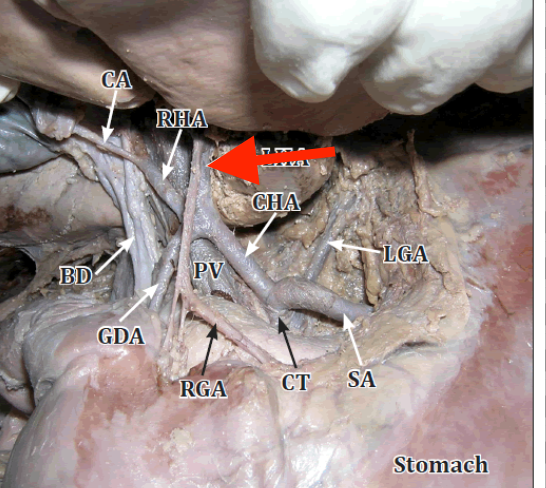

celiac trunk

left gastric artery

splenic artery

common hepatic artery

hepatic artery proper

gastroduodenal artery

porta hepatis

where the blood and lymph vessels, bile ducts, and nerves enter and leave the liver

hepatic artery proper

common bile duct

common hepatic duct

cystic duct

hepatic portal vein